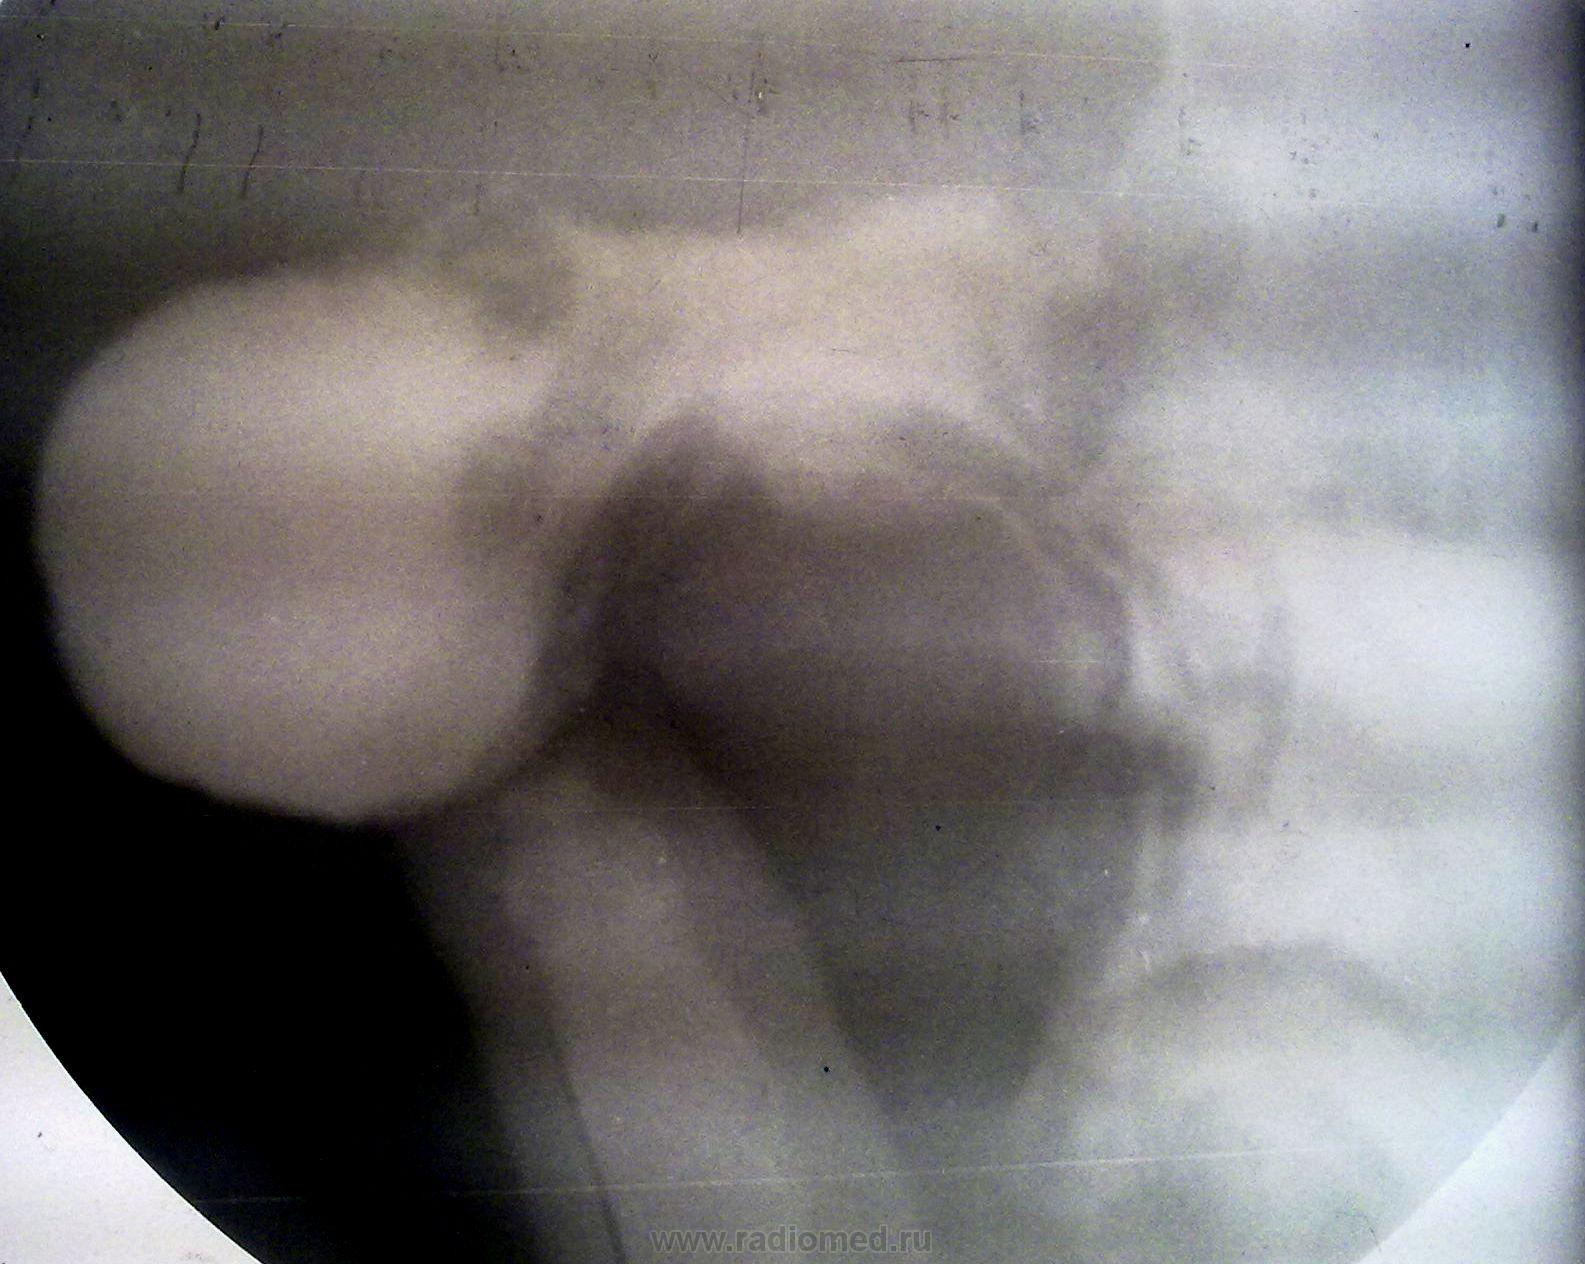

Сельский житель. На фоне полного благополучия началась рвота спустя некоторое время после принятия пищи. Из-за этого исхудал до нельзя. Никаких болевых симптомов и др. жалоб. Во время рентгеноскопии - пальпировал аж до позвоночника - не мог добиться эвакуации по 12п.к., а болей нет. Посчитал, что язв.(немая язва) стеноз. В обл.хирургии поставили рак поджелудочной и в столицу к "Шалимову". Оперировали в 2 этапа. После 1-го (я так думаю гастроэнтеростомии) начал поправляться. Сейчас все ОК (прошло уже 2 года). И все-таки, какой этиологии стеноз (обратите внимание на 5 флгр. - нисходящий отдел 12п.к. как нитка)

"И все-таки, какой этиологии стеноз (обратите внимание на 5 флгр. - нисходящий отдел 12п.к. как нитка)"

1. Луковица явно язвенная

2. На 4-й Фг так и "ниша" просматривается

3.Кто даст гарантию, что она одна?

4.Стеноз субкомпенсированый

5.За отсутствием других данных могут ли быть другие версии, кроме язвенного стеноза? как по мне - нет.

На мой взгляд, острая (свежая) язва места перехода пилорического канала в основание луковицы 12-ти перстной кишки, возможно "пилорическая язва".

Карман по большой кривизне луковицы, по всей видимости, с учетом закономерности Фанарджяна указывает также на наличие язвы по задней стенке.

Вызвал пациента на себя за свой счет. Согласно выписок: Полтавская обл.б-ца - заболевание головки панкреас, из Шалимова - хр.фибрознодегенеративный панкреатит, язв. болезнь ДПК, дуоденальный стеноз. 1-я операция - наложение гастроэнтероанастомоза, 2-я - лапаротомия + ревизия (есть фотокопии, но не привожу, т.к. на украинском языке). Чувствует себя хорошо. Приввожу рентгенограммы. Удивительно, что эвакуация наблюдается и через анастомоз и естесственным путем. И луковица воде бы нормальная. А болей как не было, так и нет.